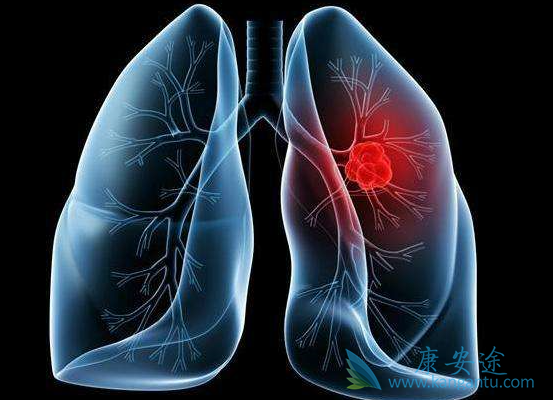

非小细胞肺癌占肺癌的80%以上,主要类型有肺癌鳞癌、肺癌腺癌和大细胞。传统治疗方面,培美曲赛+卡铂+贝伐单抗成为肺腺癌类型患者的标准一线化疗,精准放疗的优化对部分患者也可以达到与手术比肩的效果。除此之外,靶向与免疫更是此类患者的两大利刃。那么对于不可手术切除的晚期肺癌患者来说到底是该选择靶向治疗还是免疫治疗呢?

数据显示,靶向药物和免疫药物治疗肺癌需要有相应靶点方可有效。因此患者需要检测有对应靶点阳性,患者才可以使用靶向药物,或是在化疗时联合使用,以提高治疗效果。同理,免疫治疗须有PD-1/PD-L1表达,或MSI评估有明确的使用指标。具体采用哪种方案,须在主管医生的医嘱下进行。以下情况应选择靶向治疗:(1)既往经EGFR-TKI治疗时或治疗后出现疾病进展,并且经检测确认存在EGFR T790M突变。(2)ALK阳性患者。(3)BRAF V600E突变患者。(4)ROS-1突变阳性的非小细胞肺癌。

以下情况应选择PD-1免疫治疗:(1)PD-L1高表达(>50%)且EGFR或ALK无突变。(2)存在PD-L1表达(>1%)、经铂类化疗方案后疾病进展的转移性非小细胞肺癌;携带EGFR或ALK肿瘤基因突变的患者在接受FDA批准疗法后仍出现疾病进展的非小细胞肺癌。(3)与化疗(培美曲塞+卡铂)组合方案联用,用于转移性肺小细胞肺癌。(4)携带EGFR或ALK肿瘤基因突变的患者在接受FDA批准疗法后仍出现疾病进展的非小细胞肺癌。